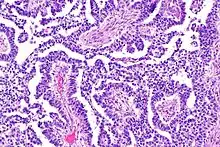

Dysgerminomas are comparable to testicular seminomas and account for approximately 32- 37% of all OGCTs.[1] They are particularly prominent in individuals with dysgenic gonads of 46, XY pure gonadal dysgenesis patients.[1] Based on gross examinations, dysgerminomas are characterized by having a ‘solid, lobulated, tan, flesh-like gross appearance with a smooth surface'.[1] Microscopically, the cellular structure is distinguished by a round-ovoid shape containing ample eosinophilic cytoplasm and an irregularly shaped nuclei.[1] The uniformly positioned cells are separated through the fibrous strands and lymphocytic infiltration is commonly observed.[5]